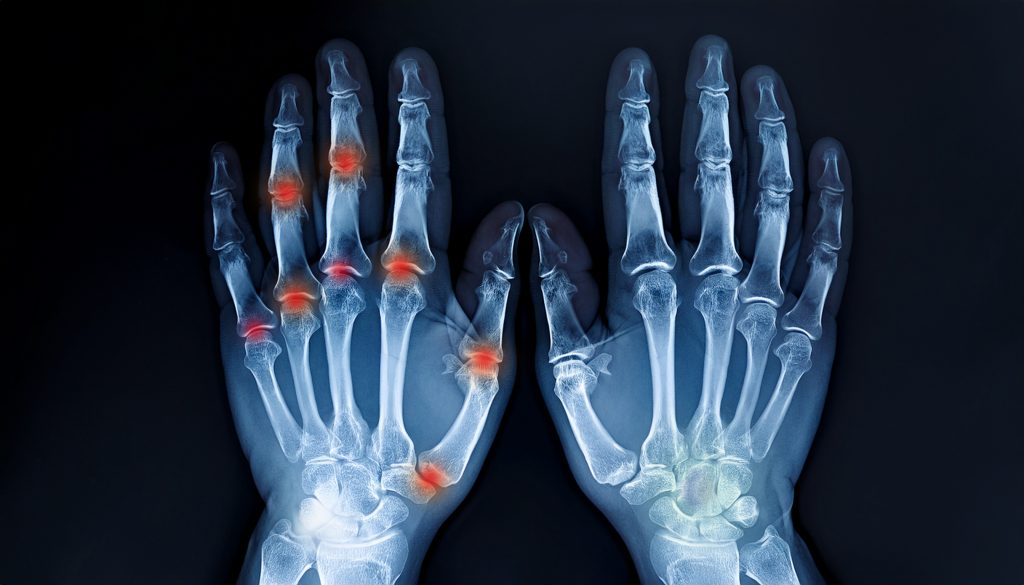

Godinama je trpjela bolove u zglobovima, trnjenje ruku i noćne grčeve koji su joj oduzimali san.

Jedna žena iz Cazina godinama je osjećala ukočenost, bol i trnjenje u rukama.

Često bi se budila usred noći jer nije mogla pomjeriti prste ili bi joj predmeti jednostavno ispadali iz ruku.